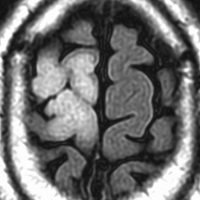

これは30歳くらいの若い女性にできた乏突起膠腫です。軽いけいれん発作を生じましたがその後は無症状です。上がT2強調画像で,下がガドリニウム増強像です。CTでは石灰化が散在していました。大脳深部をほとんど埋めるように腫瘍は浸潤して広がっています。脳外科の先生にこの患者さんが無症状だといっても信じてもらえないのですが本当です。

ほんの少しだけ腫瘍をとって(生検術)病理診断を確定しました。

腫瘍が大きすぎるので,認知機能を保つために,全脳照射30グレイとテモゾロマイド化学療法を2年しました。以来9年以上たちますが,とても頭の良い方でちゃんと働いておられます。

この患者さんから学ぶことはたくさんあります。この広範に伸展した腫瘍はおそらく10歳前後から存在したのだと想像されます。腫瘍が発見されず未治療だったからこそ,これまで通常の生活ができたのかもしれません。

また,グレード2の乏突起膠腫には限りなくグレード1に近い高分化型の腫瘍が存在するということです。乏突起膠腫は手術で完全摘出できれば治るのでしょうが,手術によって認知機能障害や高次脳機能障害を生じれば社会生活を一人ですることは難しくなります。分化型の乏突起膠腫は,正常の神経細胞や脳機能を破壊しないで浸潤増大しますから,脳の中にこんなに広がっても,何の症状も出さないということがあります。同じグリオーマでも膠芽腫などと比べれば大きな差があるのです。治療後の生存の質を考える時に,このような例があるということを思い出すことは大切です。